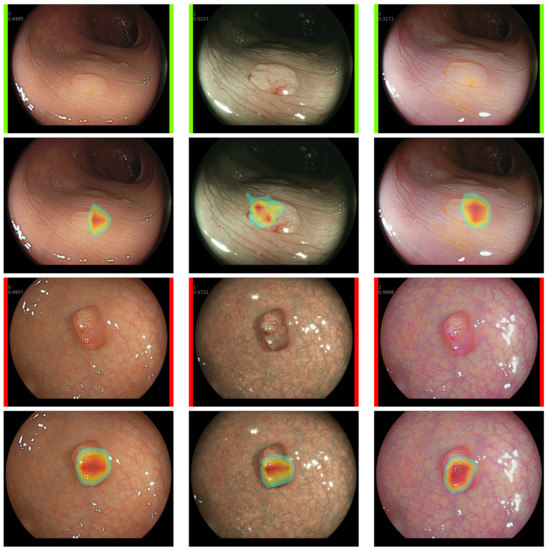

- Our developed CADx systems provides explainable visual data from the CNN to contribute to smooth decision-making.

2.5. Explainable CADx System

- Selvaraju, R.R.; Cogswell, M.; Das, A.; Vedantam, R.; Parikh, D.; Batra, D. Grad-CAM: Visual Explanations from Deep Networks via Gradient-Based Localization. Int. Comput. Vis. 2019, 128, 336–359. [Google Scholar] [CrossRef]